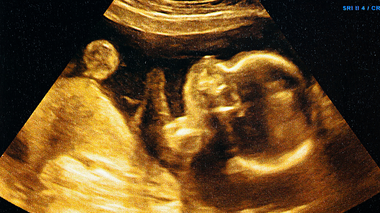

The Balance Between Progesterone and Oestrogen for Baby’s Development

Your body produces several hormones during pregnancy to support your baby's growth. Oestrogen and progesterone are the two important hormones that work together to ensure the healthy development of your baby and prepare your body for childbirth. Knowing your body well helps you spot weird changes and get help if something doesn’t feel right.

Pregnancy is a remarkable miracle, with your body doing amazing things to grow your baby. Behind these changes, a couple of hormones are at work, with progesterone and oestrogen being the shining stars. You probably already know these are pregnancy hormones. What's more exciting is how they work together to help your baby grow and keep you healthy.